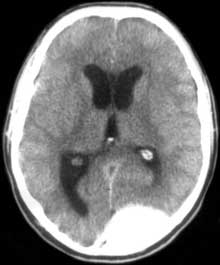

КТ головного мозга. Острая эпидуральная гематома в левой затылочной области с дислокацией головного мозга и его сдавлением.